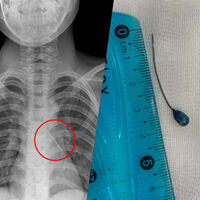

В Москве торакальные хирурги Российской детской клинической больницы спасли 11-летнего мальчика, которому булавка пронзила бронхи, ребенка экстренно доставили из Калининградской области бортом санавиации. Об этом сообщает пресс-служба медицинского учреждения.

При поступлении в больницу подросток мог говорить только шепотом и жаловался на сильные боли в груди. Рентген показал, что инородное тело находится в области нижней доли левого бронха. Вокруг булавки скопилась мокрота, а острый конец пронзил стенку бронха — это могло привести к коллапсу легкого.

Врачи отделения реконструктивной хирургии провели малоинвазивную операцию. Через эндоскоп они удалили скопления слизи, обнаружили колпачок французской булавки и с помощью оптических щипцов аккуратно извлекли инородное тело. Кровотечение было минимальным и остановилось самостоятельно. Через три дня мальчика выписали под наблюдение врачей по месту жительства.